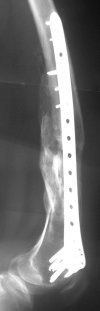

KEMMD> method of treatment for distal femur fractures

A new toy is more interesting and fashionable. And anyway it is not panacea, i have already seen presentations with LISS failures like the attached one presented by D.Seligson. And people also demonstrated incisions say that the method is not so LESS invasive as it supposed to be.